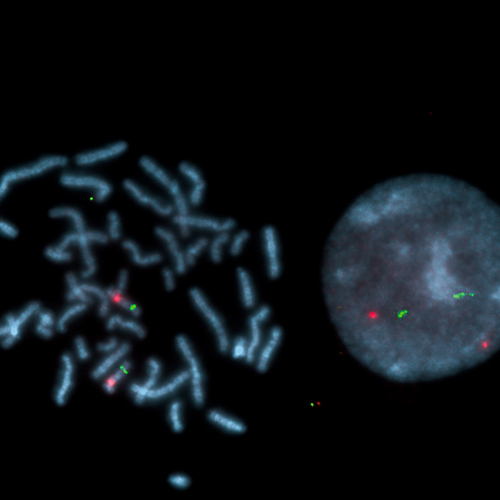

Kreatech FISH probes are the latest in advancements in FISH probes. Developed with the use of REPEAT-FREE technology, Kreatech FISH probes eliminate the use of Cot-1 or blocking DNA, providing a clearer background and a brighter signal.